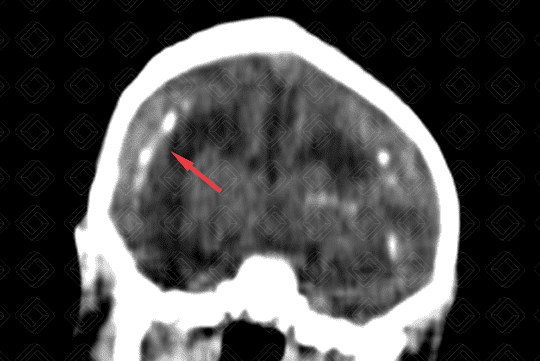

• Tomografia computadorizada do crânio evidenciando microcefalia, com importante atrofia cortical e dilatação compensatória do sistema ventricular;

• Observa-se a presença de calcificações de distribuição corticossubcortical (setas vermelhas) no parênquima encefálico e algumas menos evidentes, nos núcleos da base;